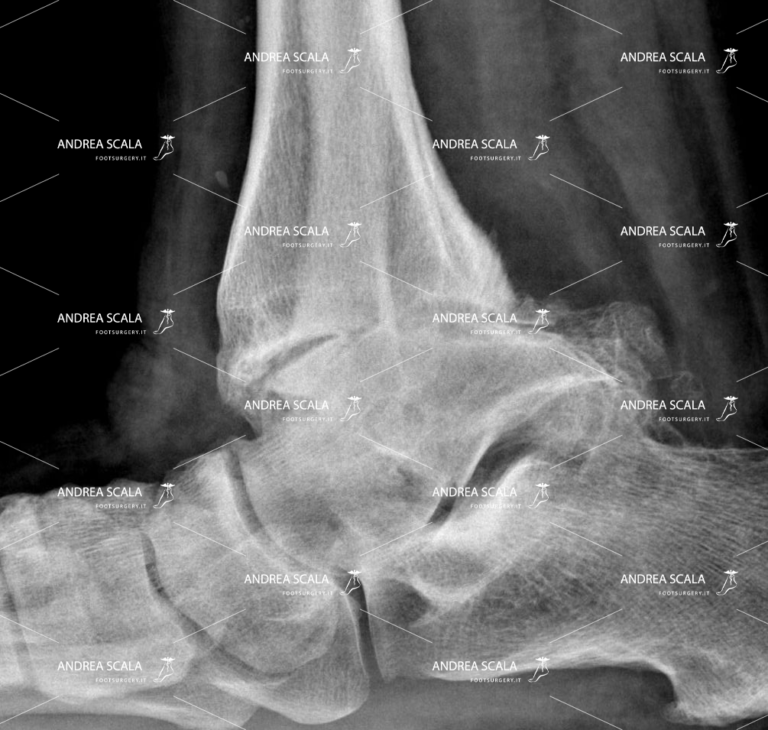

Ma cos’è esattamente l’artrosi della caviglia? Come si manifesta? Da cosa è causata? Prima di vederla nel dettaglio, è opportuno fare alcuni cenni sull’artrosi in generale. Questa patologia degenerativa, denominata anche osteoartrosi, può colpire tutte le articolazioni, le caviglie non fanno eccezione. L’ARTROSI E’ LA SCOMPARSA DELLA CARTILAGINE. La cartilagine separa le ossa e le fa scorrere senza attrito. La cartilagine viene distrutta dopo un incidente o un trauma. Oppure la cartilagine viene consumata dal reumatismo articolare.

In poche parole, l’artrosi è la scomparsa della cartilagine. La cartilagine separa le ossa e le fa scorrere senza attrito. Questa viene distrutta dopo un incidente o un trauma, oppure viene consumata dal reumatismo articolare.

L’artrosi fa sì che il nostro organismo crei un nuovo tessuto osseo (osteofiti) intorno ai legamenti interessati, il quale diventerà via via sempre più duro, causando appunto rigidità, difficoltà di movimento e dolore.

Dopo l’intervento di protesi di caviglia le ossa sono separate. Il movimento della caviglia è tornato normale e senza dolore.